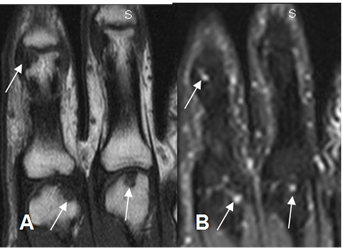

Fig 27. Artropatía reumática.

A: RM coronal en T1 y B: RM coronal en STIR. Presencia de erosiones marginales en los metacarpianos y la falanges proximales, hipointensas en T1 e hiperintensas en STIR.